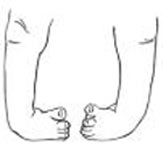

cubitus Varus clan

Cubitus Varus clin2